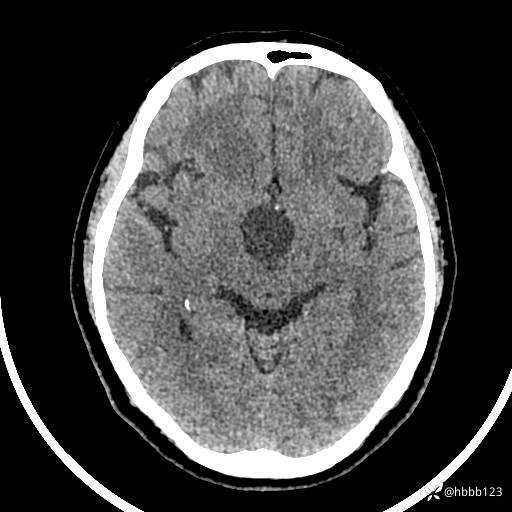

颅脑CT平扫: